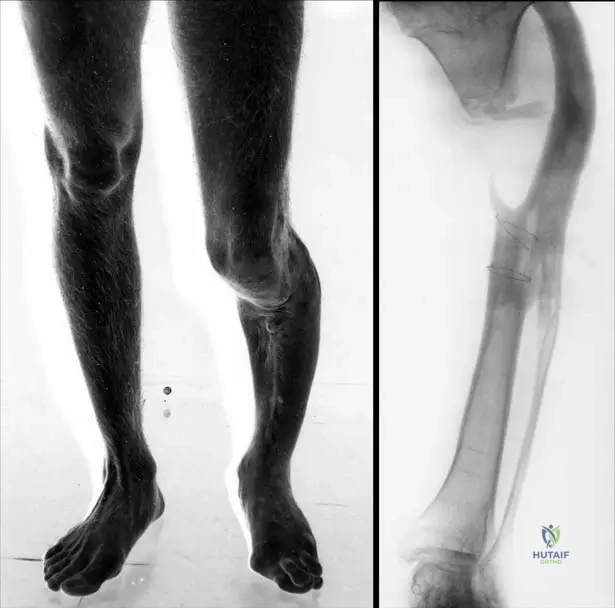

A 13-year-old male presents with an incidental finding of a nonossifying fibroma. The provided image, Fig. 11.16a, shows a characteristic location for these lesions. Which specific bone and region is depicted in Fig. 11.16a?

View Answer & Explanation

Correct Answer: C

Rationale: The image caption explicitly states, "Fig. 11.16 a–c These lesions are usually eccentric and metaphyseal, often occurring in the long bones of the lower extremity, including the distal femur (a) and distal (b) and proximal (c) tibia." Therefore, Fig. 11.16a depicts the distal femur.

Question 71

A 16-year-old female is diagnosed with an asymptomatic nonossifying fibroma. The provided image, Fig. 11.16b, illustrates another common location for these lesions. Which specific bone and region is depicted in Fig. 11.16b?

Correct Answer: B

Rationale: The image caption explicitly states, "Fig. 11.16 a–c These lesions are usually eccentric and metaphyseal, often occurring in the long bones of the lower extremity, including the distal femur (a) and distal (b) and proximal (c) tibia." Therefore, Fig. 11.16b depicts the distal tibia.

Question 72

A 10-year-old male presents with an incidental finding of a nonossifying fibroma. The provided image, Fig. 11.16c, demonstrates a third common location for these lesions. Which specific bone and region is depicted in Fig. 11.16c?

Rationale: The image caption explicitly states, "Fig. 11.16 a–c These lesions are usually eccentric and metaphyseal, often occurring in the long bones of the lower extremity, including the distal femur (a) and distal (b) and proximal (c) tibia." Therefore, Fig. 11.16c depicts the proximal tibia.